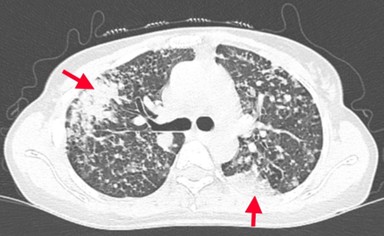

CASE LÂM SÀNG Điều trị bệnh nhân mắc đồng thời hai loại ung thư: Ung thư phổi và ung thư tuyến tiền liệt

CASE LÂM SÀNG Điều trị bệnh nhân mắc đồng thời hai loại ung thư: Ung thư phổi và ung thư...